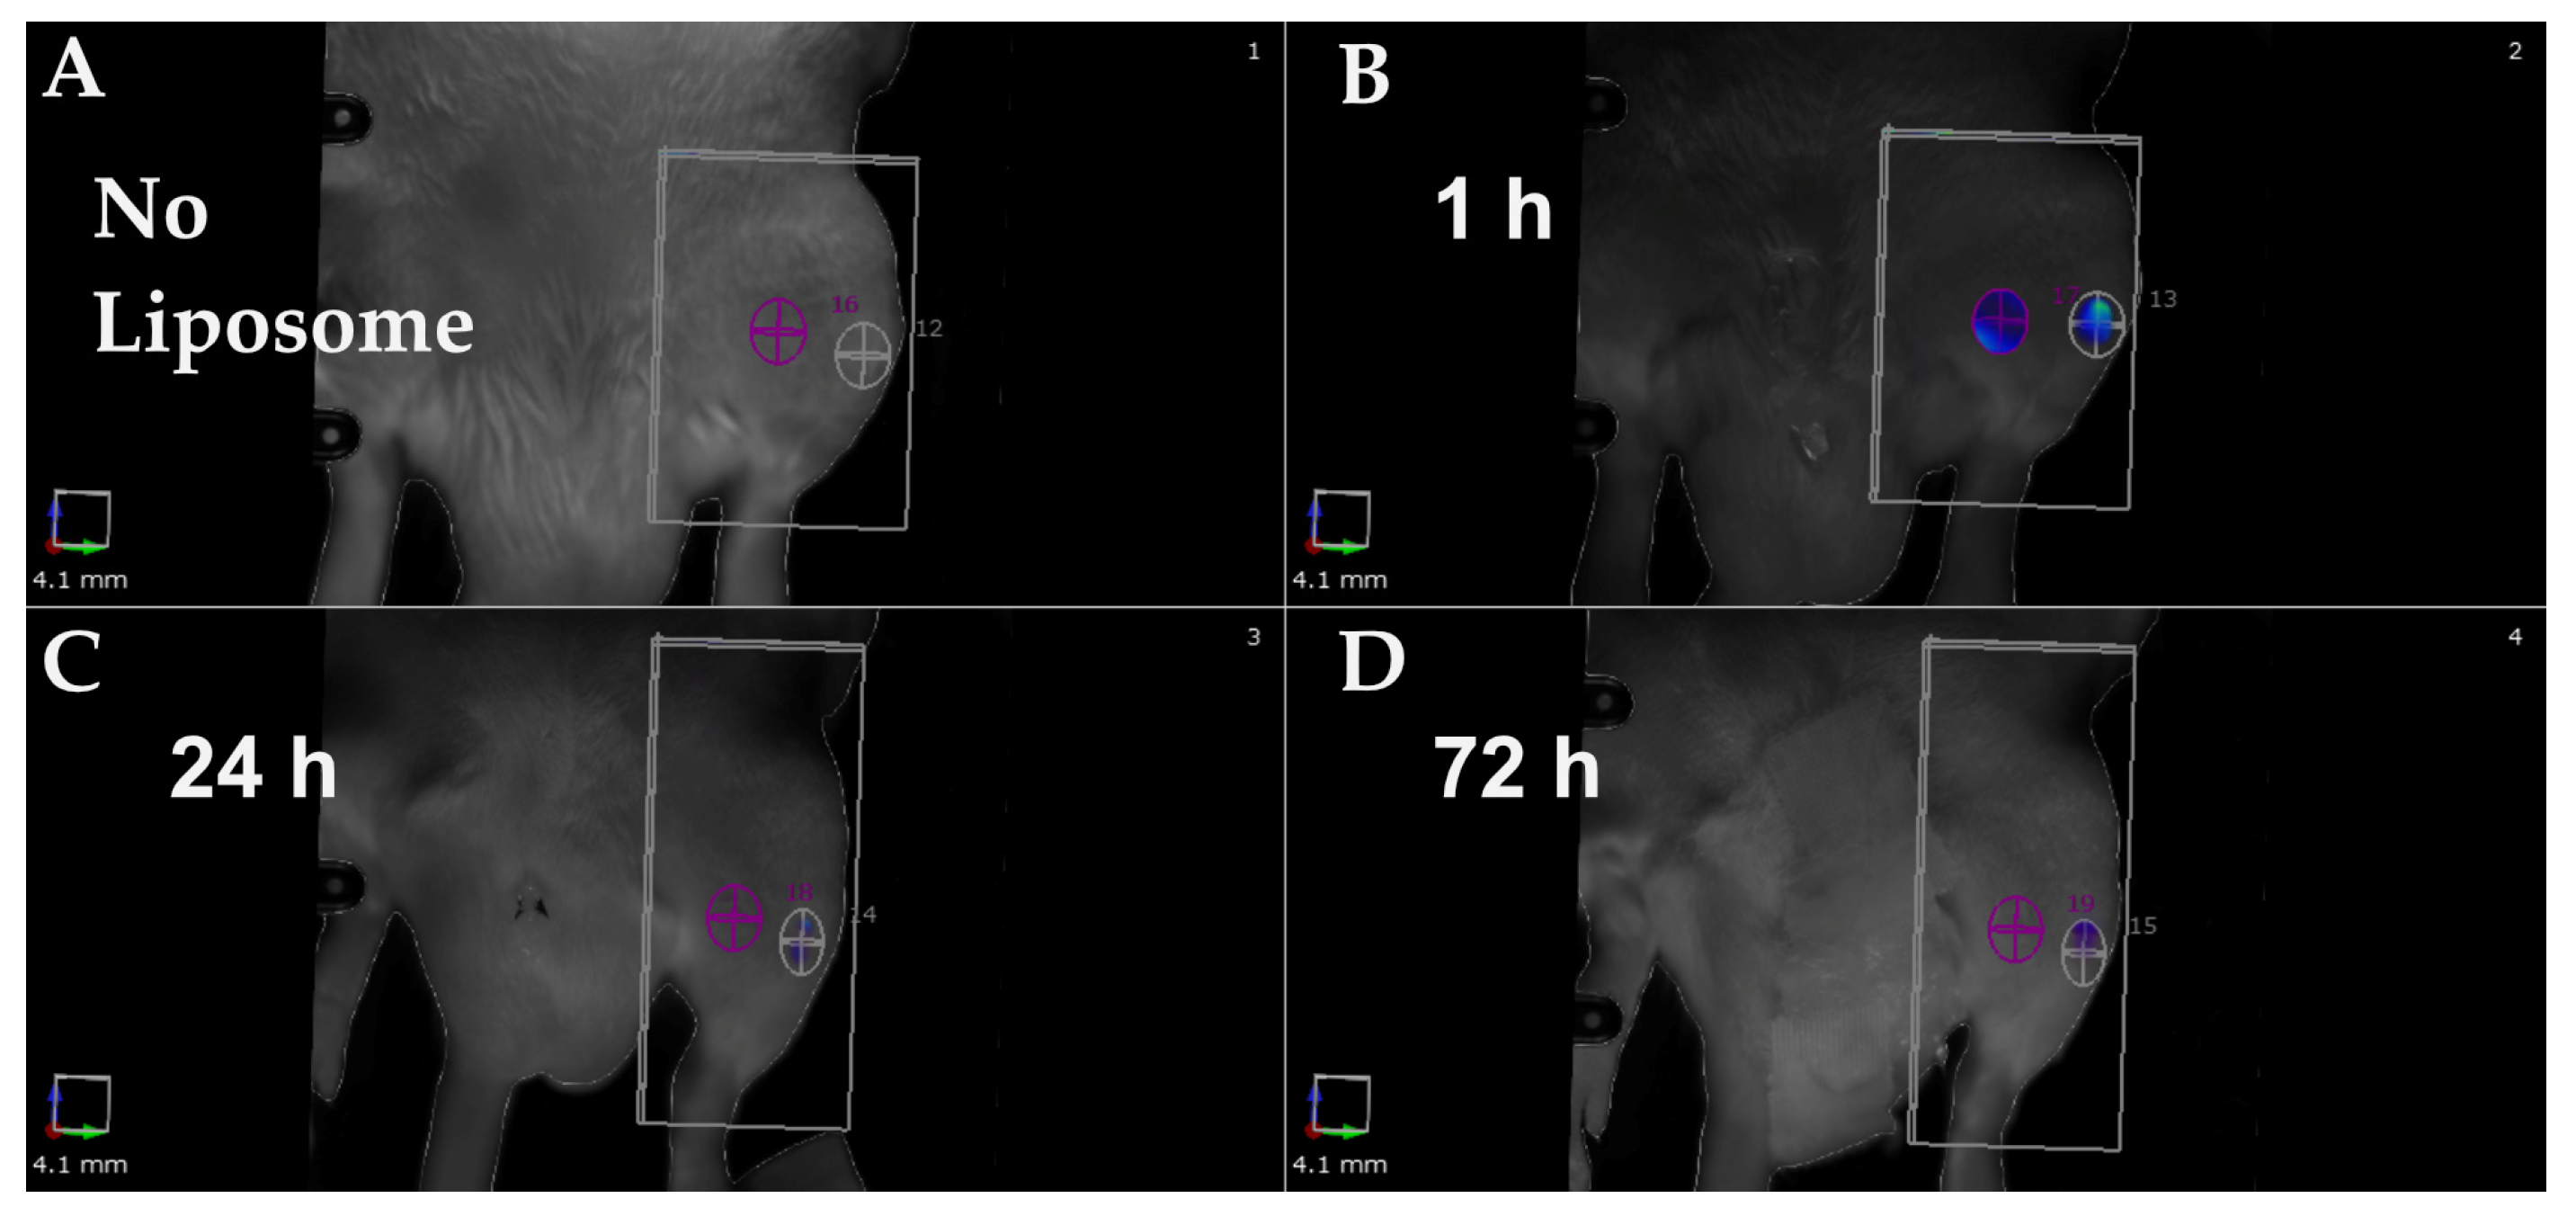

2.2. In Vivo Evaluation of α-MSH-SM-Liposomes

4.6. Imaging of α-MSH-SM-Liposomes